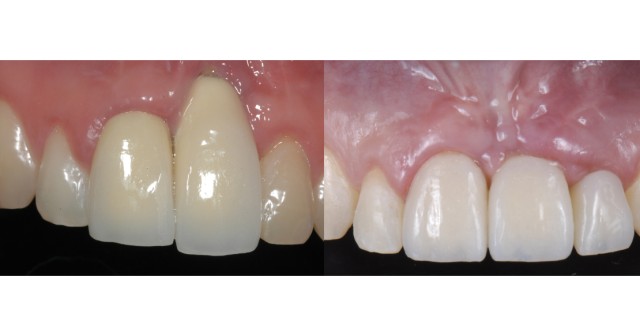

Managing Implant Challenges in the Esthetic Zone

Gingival and contralateral symmetry are important considerations, especially when placing more than one implant.By Ricardo Mitrani